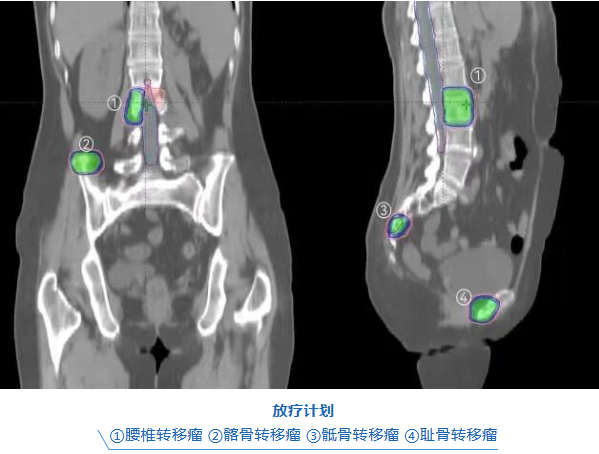

面对多处转移的复杂病情,肿瘤六科陈意标主任医师团队通过多学科会诊,为她制定了个体化的精准放疗方案:仅通过一次CT定位、实施五次治疗,即同时精准覆盖四个骨转移灶。

一次定位,全面规划:通过一次CT定位,同步精准勾画四个骨转移靶区。

高剂量精准打击:采用立体定向放疗(SBRT),犹如狙击手,对肿瘤实施高剂量、高精度照射。

实时影像引导+自适应调整:每次治疗前均进行CBCT影像引导,结合在线自适应放疗技术,实时调整照射参数,确保射线完美覆盖肿瘤,同时避开脊髓等重要器官,最大限度保护正常组织。